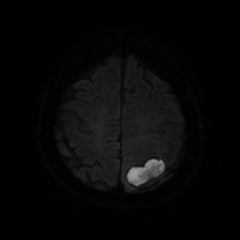

Caso neurorradiología

Paciente de 60 años con cuadro de 1 semana de evolución consistente en tropiezos frecuentes y alteración en la movilidad del miembro

inferior derecho. No refiere

cefalea u otros síntomas asociados, no pérdida de peso, no náuseas o emesis, no

sudoración nocturna. Antecedentes de hipertensión arterial y diabetes.

Resonancia magnética